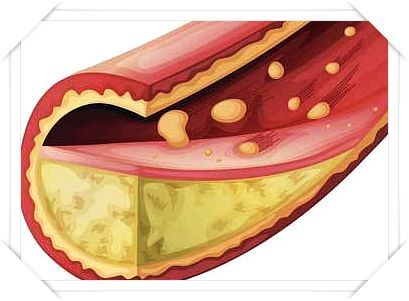

LDL(나쁜 콜레스테롤) 수치가 높게 나오면

동맥벽에 기름때가 쌓여 혈관이 좁아지고 탄력을 잃게 됩니다.3. 피로감과 무기력증

고지혈증 증상 10. 심근경색 또는 뇌졸중 위험 증가

고지혈증을 방치하면, 혈관 속에 플라크가 쌓이고,

이것이 혈전을 만들어 혈관을 막아버릴 수 있어요.

결과적으로 심근경색, 뇌졸중(뇌경색) 같은 치명적 질환으로 이어질 수 있습니다.

이런 상태에 이르기 전에 관리가 꼭 필요합니다.고지혈증 주의사항